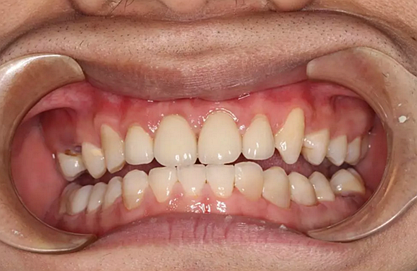

現(xiàn)在剩下的任務(wù)就是為我其他的兄弟姐妹們治療了。需要做根管的做根管,需要做冠的做冠,需要樹脂充填的做樹脂充填。前前后后主人帶我們進行了12次的復(fù)診,歷時6個月,現(xiàn)在的我們是這樣的

再來看看曾經(jīng)的我們